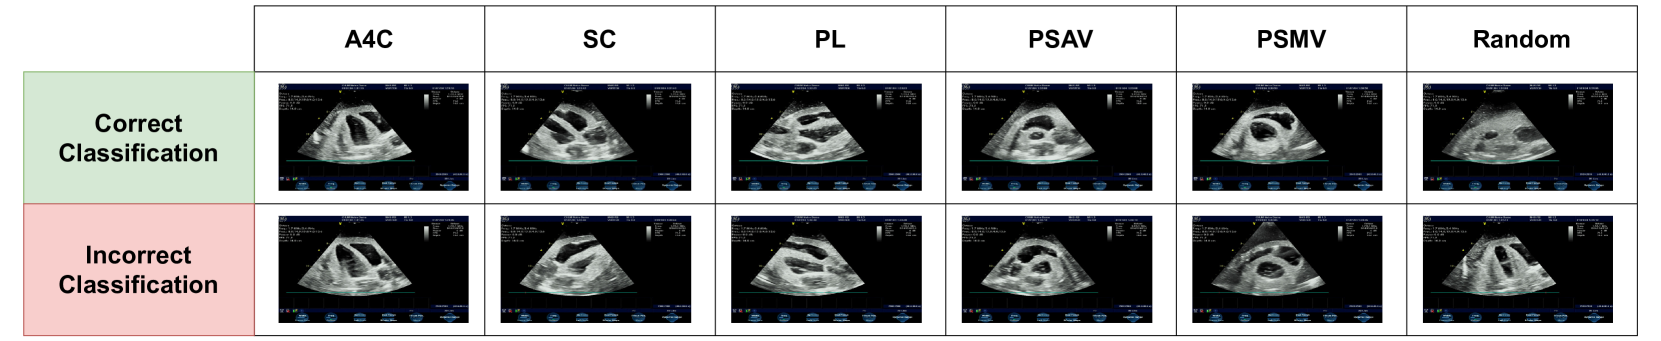

To evaluate the proposed AI framework, we also conducted real-time scans, providing the framework with real-time cardiac US images. For these real-time experiments, we kept the same US parameters for all views. We obtained the results from the AI model and compared them with expert feedback in terms of classification accuracy and grading loss. Based on the results, we observed that all cardiac views were accurately classified, with classification accuracy reaching up to 96%, and with rare challenges faced for the Random and PSAV classes. For the Random class, there were few scenarios where the model misclassified a view as Random due to its low quality. While an expert can identify the cardiac view (even if it is incomplete), the model classifies it as random due to the low quality. As for the PSAV class, it was challenging for the model to detect it in certain scenarios due to the absence of dynamic valves and the static nature of the cardiac phantom, making it difficult sometimes to be differentiated from random views. Therefore, in the future, acquiring a phantom with dynamic valves would be a valuable approach, enabling more precise differentiation between the PSAV view and other views. Figure 19 shows the classification results during real-time scans, including both correct classification results and cases of misclassification. As generally shown in the figure, misclassifications are typically incorrectly classified as Random. An image that should be classified as Random is sometimes classified as A4C, which is due to the nature of the phantom that does not allow for precise differentiation between the A4C class and the Random class. The same issue applies to the PSAV class.

Refer to caption

Fig. 19: Real time scans: examples of classification results